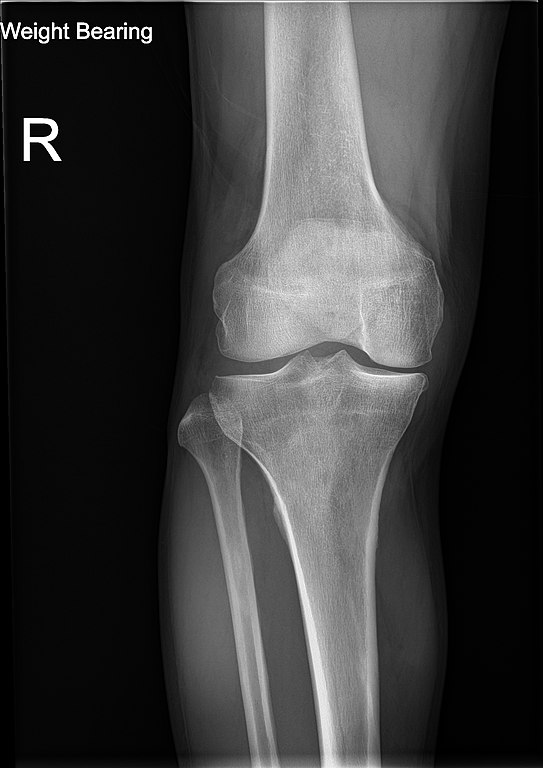

File:Knee plain X-ray weight bearing.jpg - WikipediaCada año, los especialistas médicos solicitan radiografías para diagnosticar enfermedades y lesiones en millones de personas. A pesar de su prevalencia, los rayos X se malinterpretan y, a menudo, se perciben como peligrosos debido a la radiación utilizada para crear las imágenes. No ayuda que usted también tenga que usar un delantal de plomo grande y pesado, y el técnico se apresura a salir de la habitación antes de tomar la radiografía.

Cuando tiene una radiografía, se para o se acuesta entre la fuente de rayos X y el detector. La fuente de rayos X envía radiación electromagnética a través de su cuerpo y hacia el sensor, que crea la imagen de sus huesos y otras estructuras internas.

Los rayos X pueden crear imágenes del interior de su cuerpo porque sus diversos tejidos absorben diferentes cantidades de radiación a medida que el haz pasa a través de su cuerpo. Sus huesos absorben la mayor parte de la energía mientras que sus pulmones llenos de aire no absorben casi nada.

La imagen de rayos X es como una silueta. Dado que sus huesos absorben la radiación y bloquean su paso, el detector recoge la radiación que pasa por sus huesos o pasa a través de otros órganos.